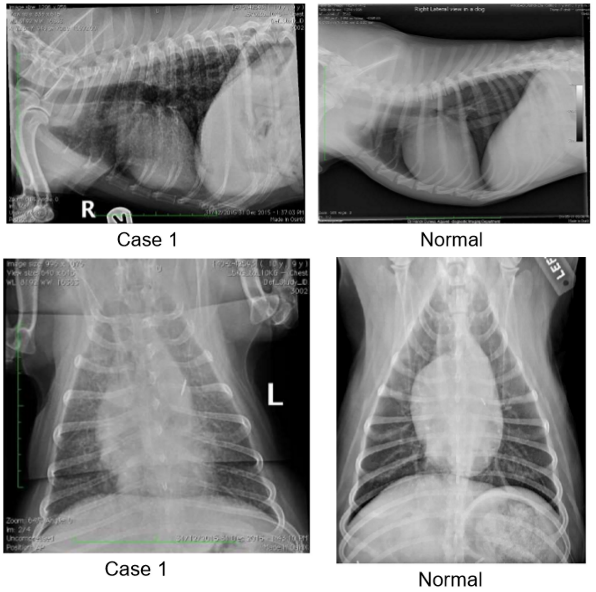

• what pattern is present in this case?

interstitial

• what pattern can be seen below?